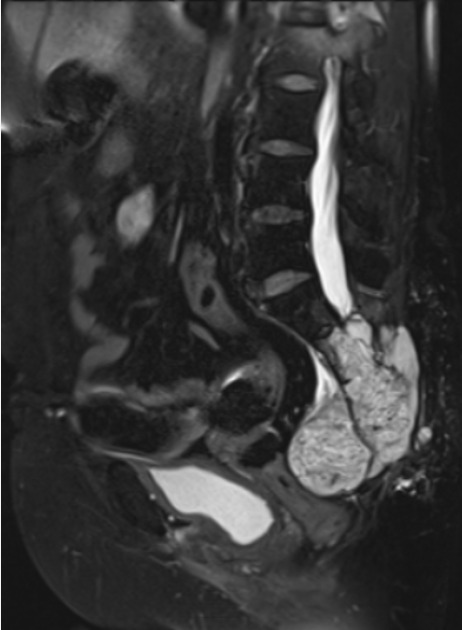

Sarcoma de Ewing: é o segundo tumor ósseo maligno primário dentre crianças, adolescentes e adultos jovens. Mais frequente em ossos longos como fêmur, tíbia e úmero, além dos ossos da bacia, escápula e coluna vertebral.

A avaliação de um médico especializado é fundamental para um diagnóstico correto. Devido a sua raridade e poucos sintomas, o diagnóstico é difícil e pode ser retardado. O exame físico minucioso e a avaliação da história clínica são importantes para a diferenciação de tumores para outras doenças mais comuns, como abscessos, infecções, doenças inflamatórias e vasculares. A Ressonância Magnética é o melhor exame para investigação de tumores de partes moles, proporcionando uma boa percepção da anatomia local e características do tumor. A biópsia através de agulha ou por meio de incisão pode ser indicada para auxiliar o diagnóstico e guiar o tratamento definitivo.